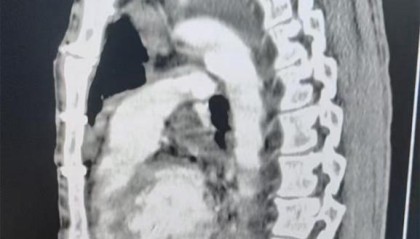

男子被12厘米钢丝刺入心脏,没想到3年前手术后形成的“保护层”救了他

近日,长沙一男子意外被钢丝刺入心脏,钢丝贯穿多个心腔并形成血栓,男子命悬一线。...